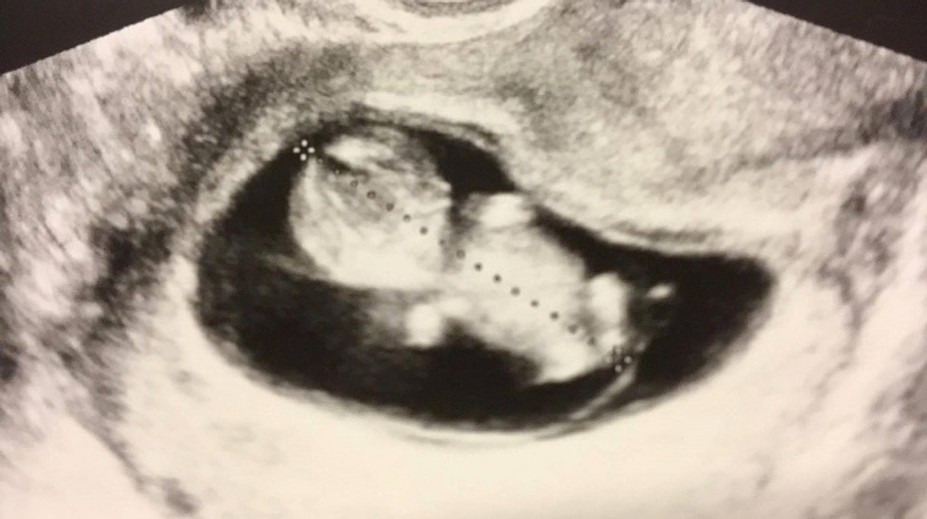

Júlia Horváthová